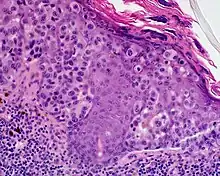

Lentigo maligna melanoma is a melanoma that has evolved from a lentigo maligna,[1]: 695 as seen as a lentigo maligna with melanoma cells invading below the boundaries of the epidermis.[2] They are usually found on chronically sun damaged skin such as the face and the forearms of the elderly.

Lentigo maligna is the non-invasive skin growth that some pathologists consider to be a melanoma-in-situ.[3] A few pathologists do not consider lentigo maligna to be a melanoma at all, but a precursor to melanomas. Once a lentigo maligna becomes a lentigo maligna melanoma, it is treated as if it were an invasive melanoma.

An invasive tumor arising from a classical lentigo maligna. Usually a darkly pigmented raised papule or nodule, arising from a patch of irregularly pigmented flat brown to dark brown lesion of sun exposed skin of the face or arms in an elderly patient.